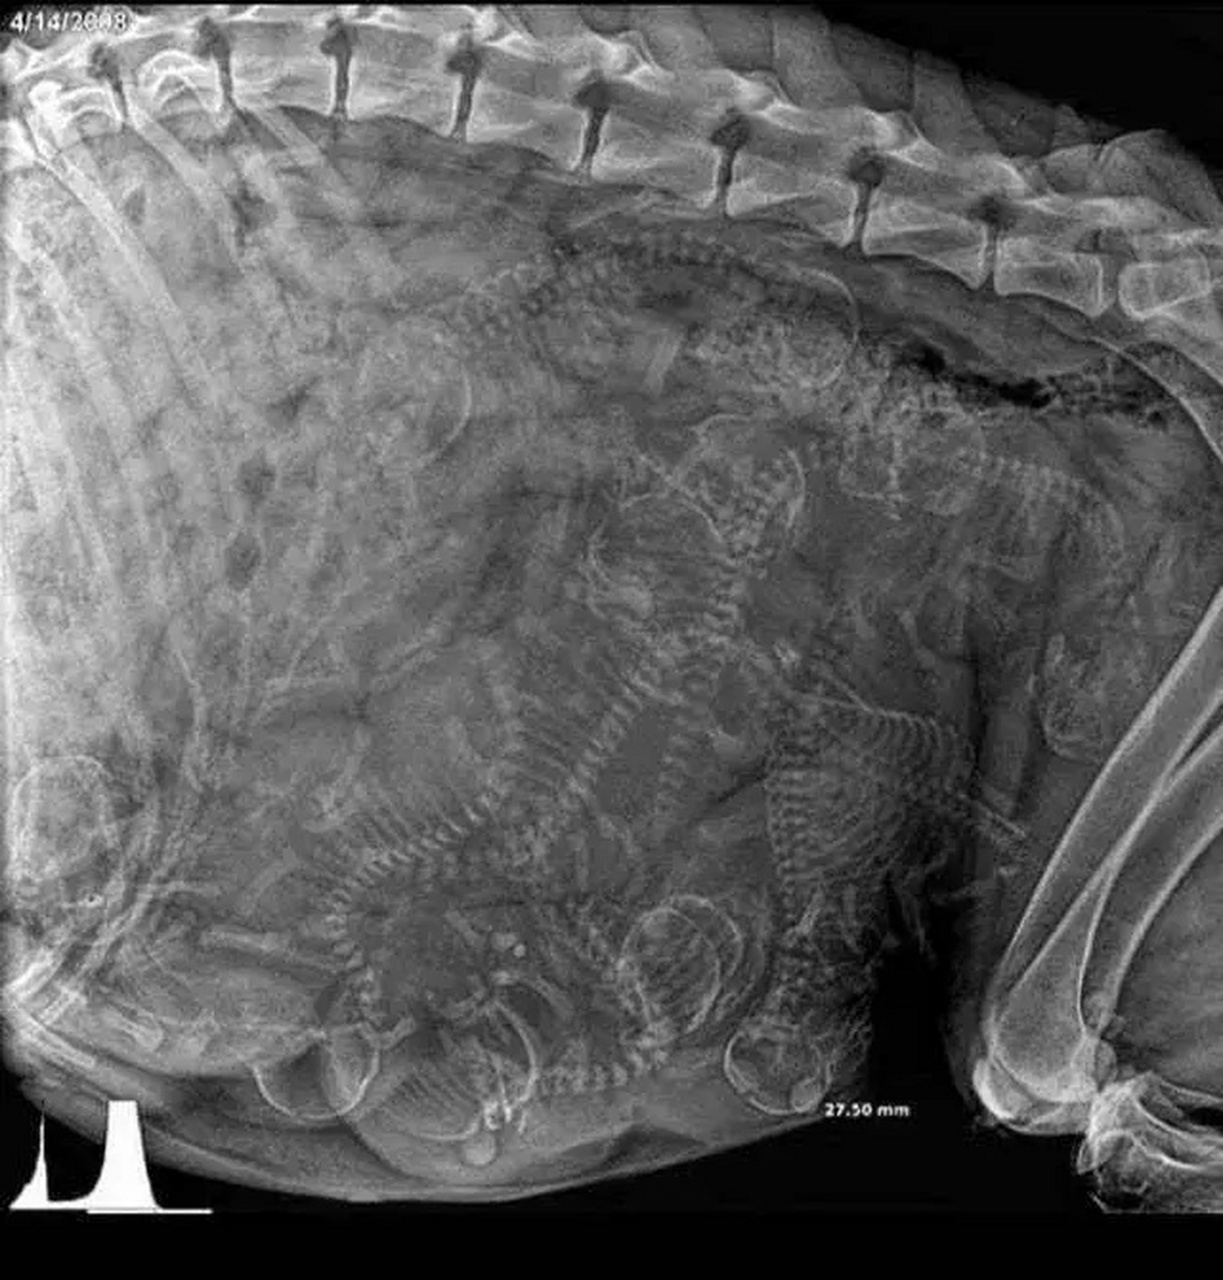

怀孕的狗的x光片,大家数数肚子里有几只狗宝宝#动态创作月

怀孕狗狗的x光照片.